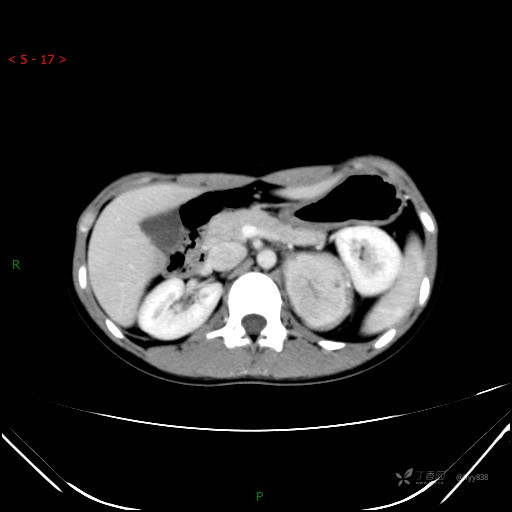

腹部CT平扫